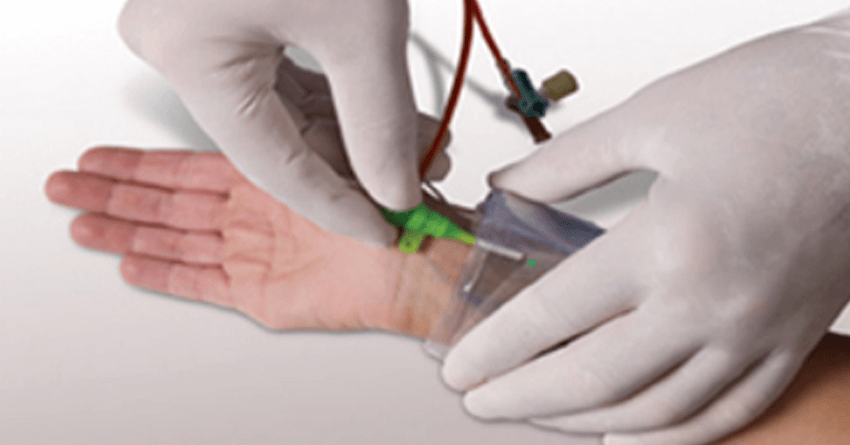

Post-procedure there are certain rare complications such as the development of bleeding at the arterial puncture site in cases of angiography and angioplasty via femoral artery near the groin region. The reported incidence of bleeding and hematoma formation is higher with cardiac procedures from leg artery. So, I perform a majority of procedures through the hand artery which is known as Radial angioplasty, which leads to very less complication at the access site as shown in the figure below.

Radial Angioplasty: The image shows the removal of the radial sheath after angioplasty and application of compression using the radial compression band. This band is removed after 5-6 hours, which minimizes the access site complications like bleeding or hematoma formation.

Bleeding: Blood-thinning medications which are called as ‘antiplatelet and anticoagulants’ are given to patients to prevent the development of the fresh clot formation at the site of angioplasty where the stent was deployed by the surgeon. This may lead to bleeding from the access site (the site where the artery was punctured) particularly, in the access sites in the groin.

But we perform Radial angioplasty, which minimizes the risk of bleeding to as low as 1%. Also, we perform snuffbox access, which reduces the risk of access site complication to the bare minimum. The ultrasound guidance gives us a proper puncture point. The team of interventional radiologist and vascular surgeon help us in planning access before the procedure and management of access site complication.